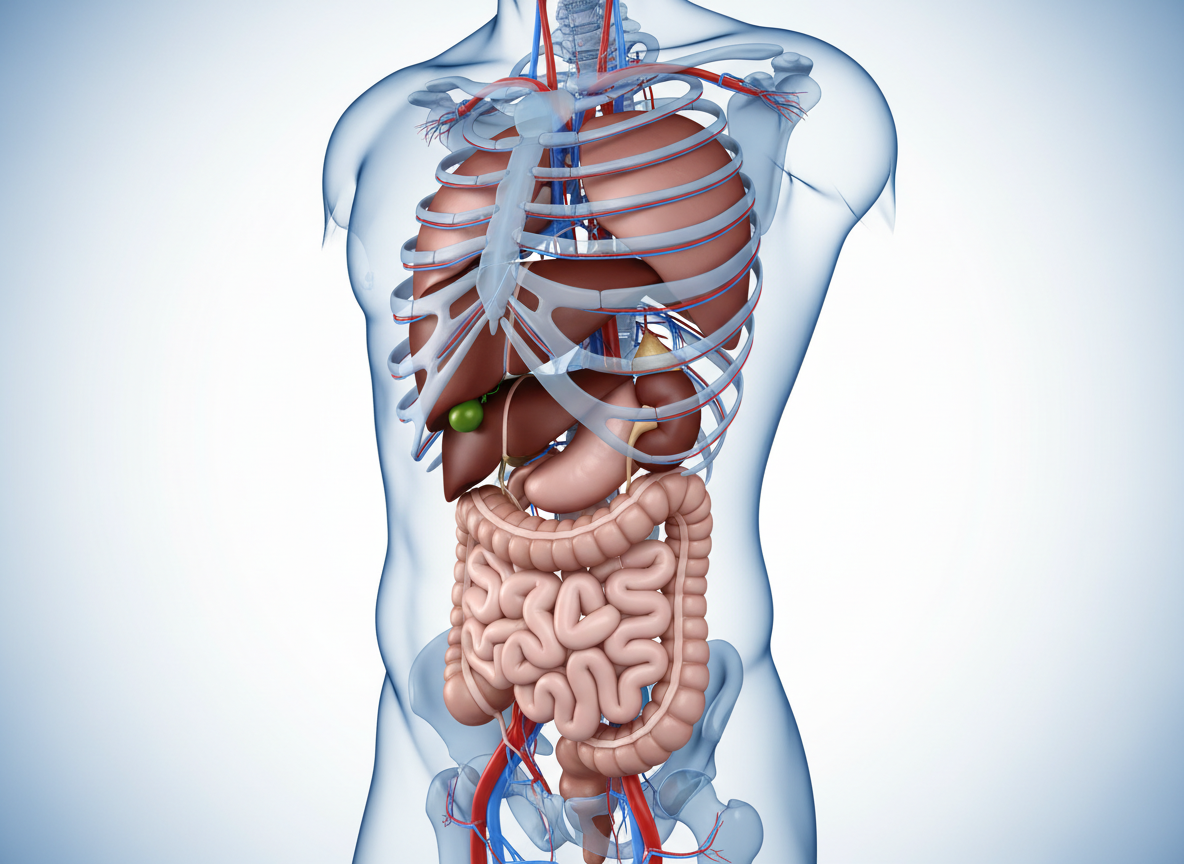

오른쪽 옆구리 안쪽에는 신장(콩팥), 요관, 담낭(쓸개), 간, 맹장 등 우리 몸의 아주 중요한 장기들이 모여 있습니다. 그래서 이 부위가 아프다는 것은 단순한 근육 뭉침일 수도 있지만, 때로는 우리 몸속 장기가 보내는 다급한 구조 요청일 수도 있어요. 오늘은 이 글을 통해 제 경험과 전문적인 지식을 바탕으로, 오른쪽 옆구리 통증을 유발하는 대표적인 질환들을 알기 쉽게 하나씩 짚어보도록 할게요! 😊